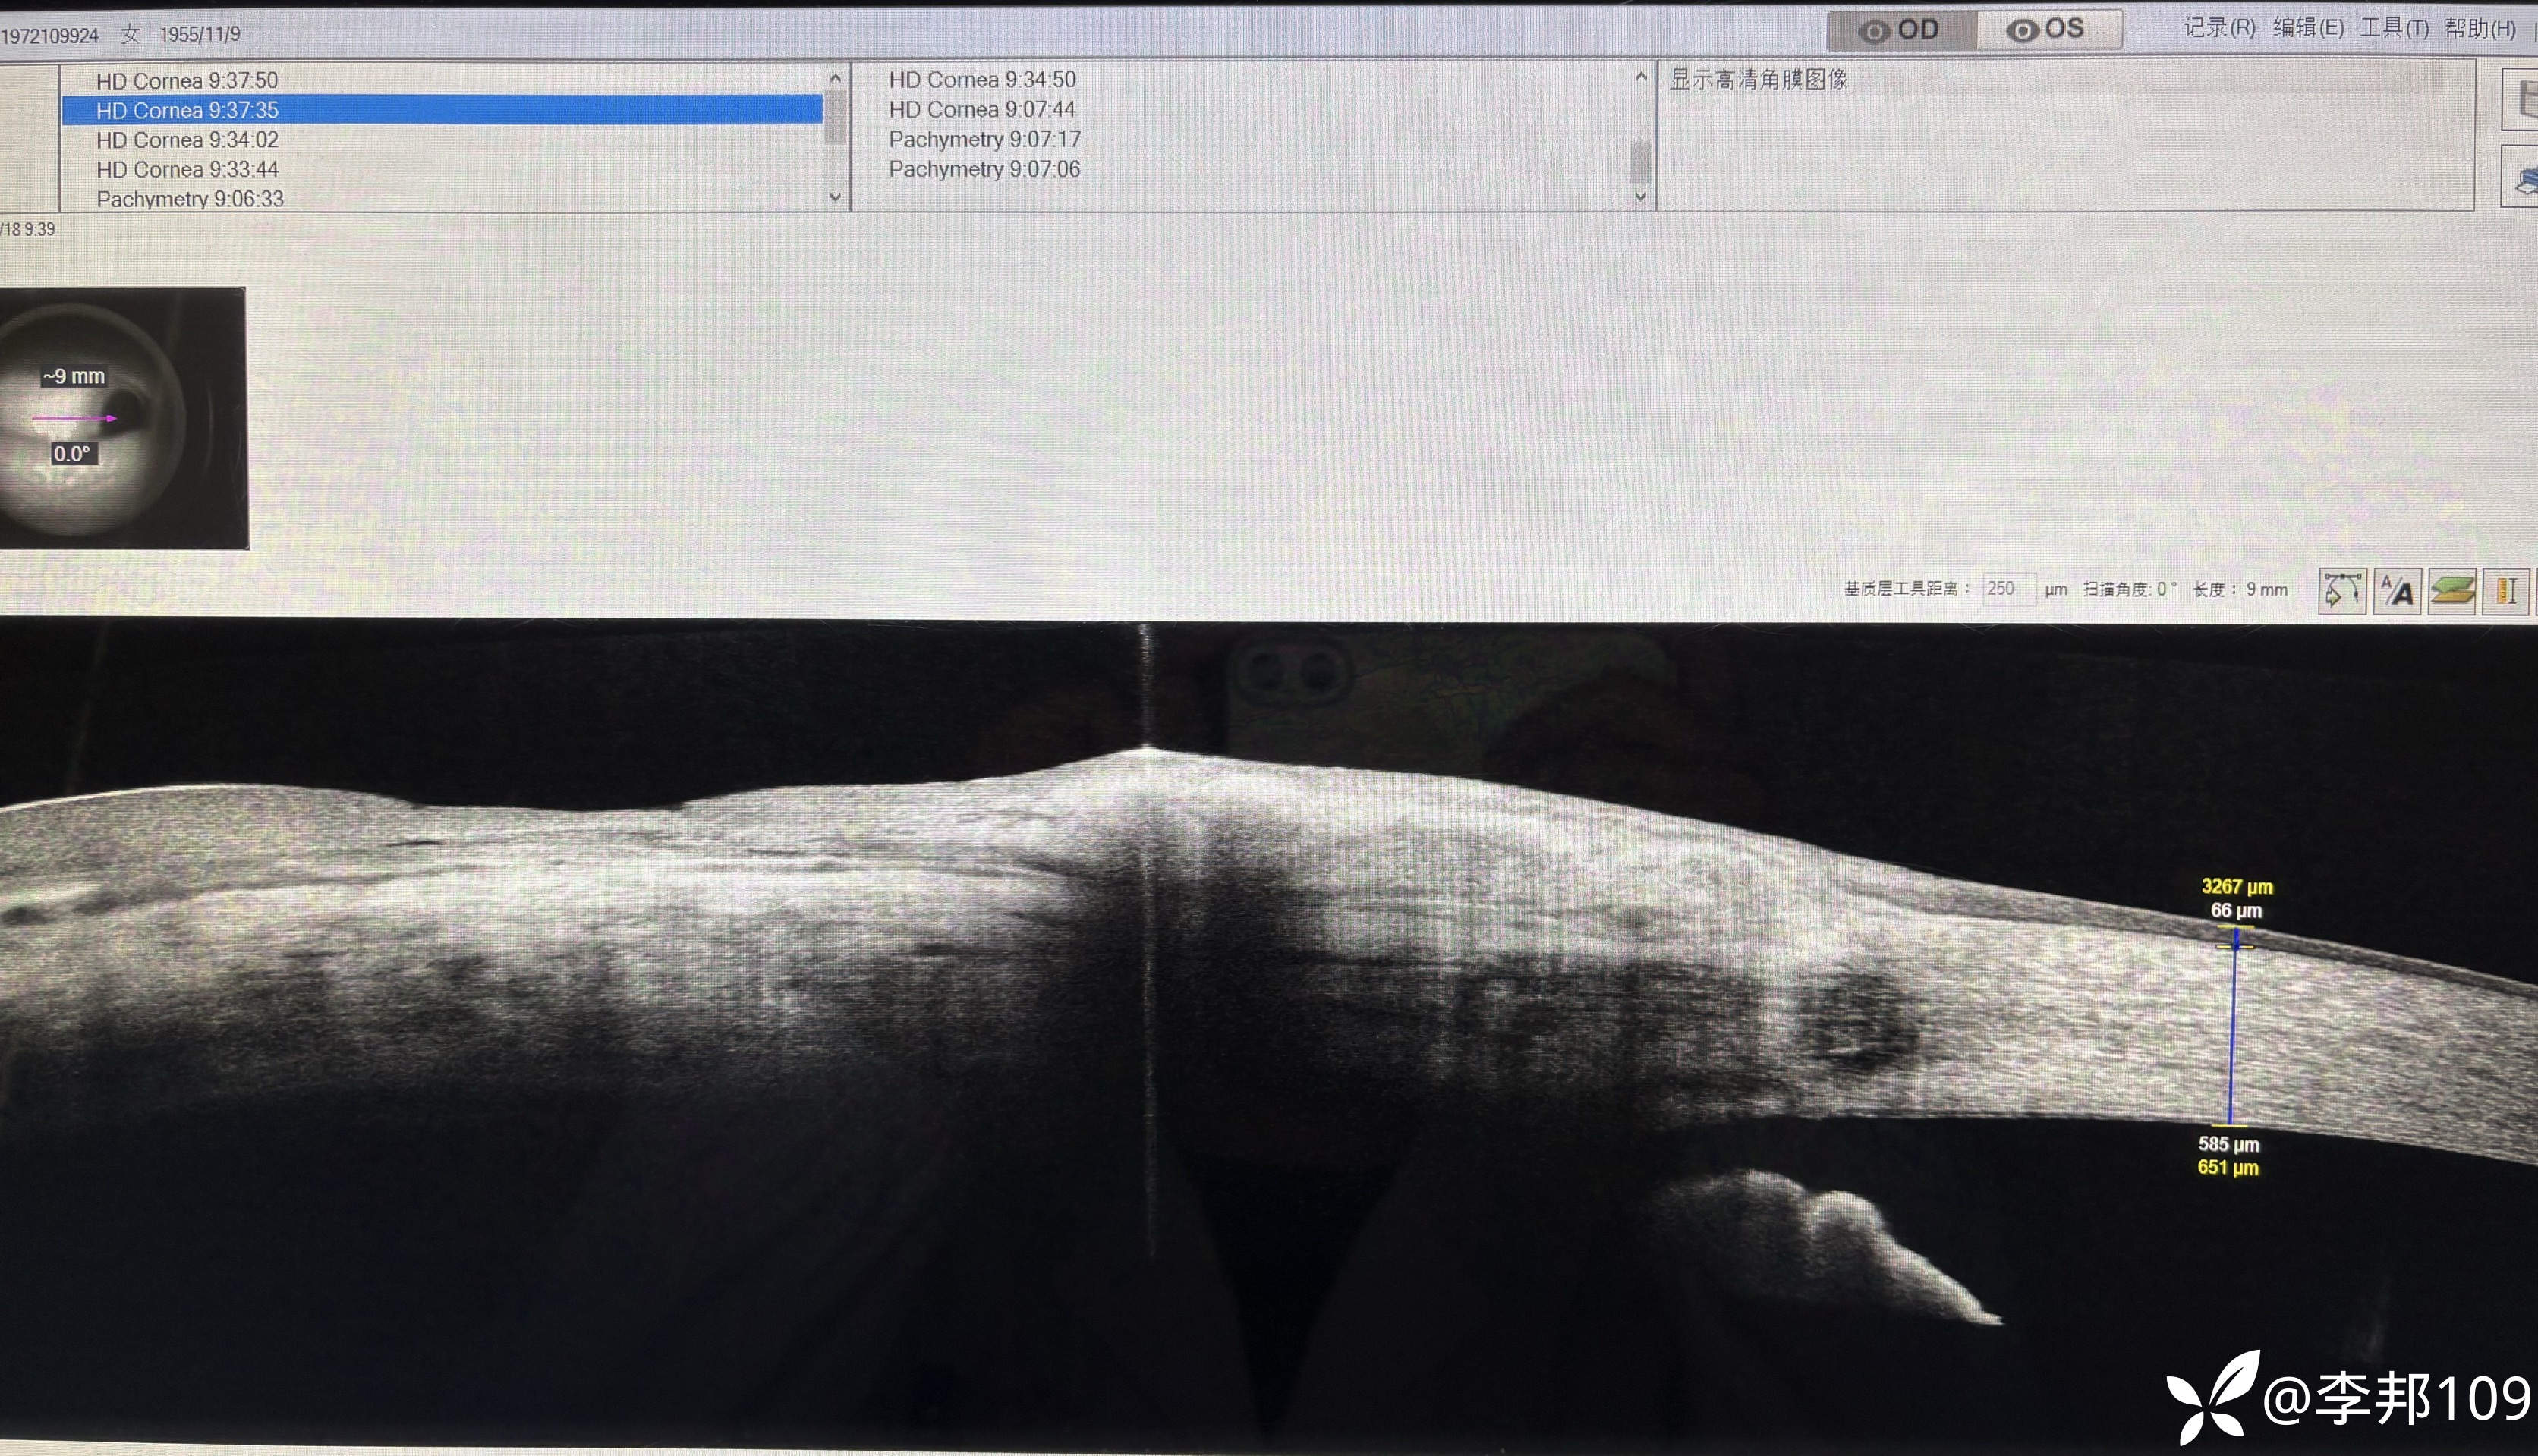

觉得不对劲,做了个AS-OCT,看看“”胬肉“”区的角膜上皮明显增厚

中央的上皮也增厚;颞侧上皮也增厚了

以为是睑裂班附近的角膜上皮是增厚的;于是做了一下右眼作对比,右眼不增厚;

双眼角膜上皮厚度不一样,干脆又做了一个角膜上皮厚度检查;

左侧角膜上皮厚度明显增厚;

散光来源于上皮增厚?会有这么明显吗?

还有她的人工晶体是板型攀-人工晶体,短边是在水平位,人工晶体的作用力撑出来的散光?

角膜上皮or人工晶体位置or之前的手术切口